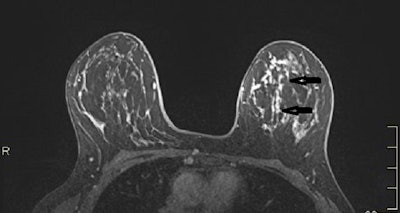

A 53-year-old woman with previous right mastectomy and uniporous left bloody discharge. Above: MRI axial plane after injection with fat saturation shows a left nonmass enhancement with linear distribution in the inner inferior quadrant (arrow). Below: Second-look ultrasound demonstrates three ducts of normal caliber in correlation (arrow). 10-G vacuum-assisted biopsy under ultrasound guidance revealed papilloma removed by surgical excision. Images courtesy of Dr. Martine Boisserie-Lacroix and European Radiology.MRI detected a lesion requiring excision in 46 participants (45%) with unexplained discharge, and if a breast MRI scan is negative, follow-up is a safe alternative for these patients, the authors wrote in an article published on 13 April in European Radiology.